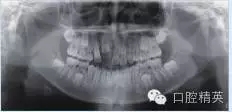

輔助檢查:全頜曲面斷層片顯示左側下頜骨體部可見類圓形高密度影,周圍可見低密度影環(huán)繞(圖1a);CT顯示:左側下頜骨體部呈膨脹性骨質改變,局部骨皮質變薄,內伴高密度骨質硬化影,邊界尚清晰,周圍軟組織腫脹(圖1b)。

圖1 a:全頜曲面斷層片;b:CT影像

入院檢查:混合牙列,11-12牙區(qū)見唇腭側牙槽骨膨隆,腭側較明顯,表面黏膜顏色正常,觸診質地硬,無壓痛感。輔助檢查:全頜曲面斷層片及CT顯示11牙胚存在,其冠方牙槽骨內高密度團塊影,周圍可見低密度帶,與周圍骨組織分界清(圖2a、b)。

圖2 a:全頜曲面斷層片;b:CT影像